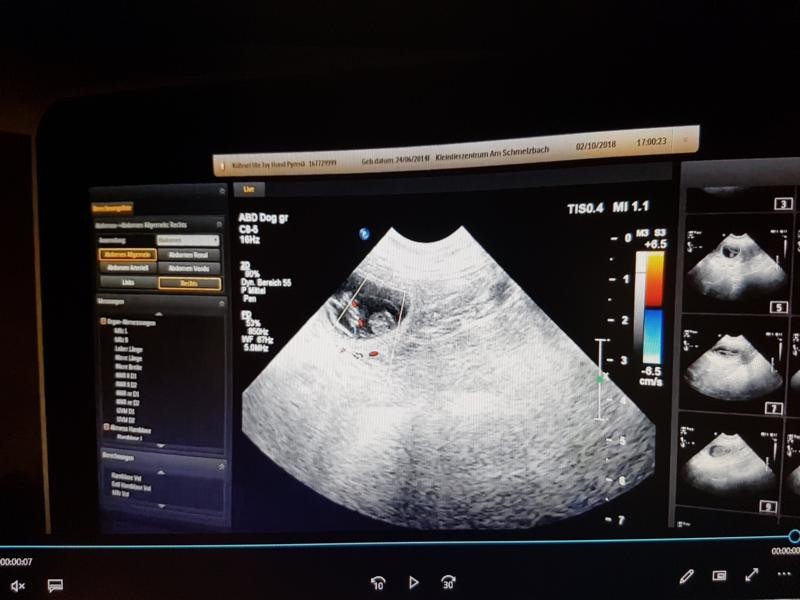

Wieder zuhause – Fin hat es in unserer Abwesenheit Herrchen nicht leicht gemacht – er hat einen Teil seines Rudels vermisst – Herrchen musste leiden. Jetzt, wo alle wieder da sind, er aber seine Ivy nur riechen, hören aber nicht sehen darf – wird er trotzdem entspannter und langsam zieht Ruhe ein. Da Ivy immer noch gut riecht und jetzt auch noch nach Nobel duftet, dürfen Fin und sie sich nicht begegnen. Wir sind gespannt – hoffentlich hat alles geklappt. Wir beobachten Ivy genau – sie fängt sehr schnell an sich zu einer absoluten Schmusebacke zu entwickeln, will immer kuscheln, könnte den ganzen Tag schlafen und auch ihr Appetit ist langsam nicht zu bremsen. Auch schon, als sie mit den Zwergis ihres A-Wurfs trächtig war, klaute sie das frische Brot von der Arbeitsplatte in der Küche, stand da um irgendwas „Fressbares“ ergattern zu können – man könnte denken, sie verhungert sonst. Ja, das sind schon Anzeichen – aber auch bei Scheinträchtigkeit kann es dazu kommen diese Anzeichen zu entwickeln. Wir beobachten jede noch so kleine Veränderung, hoffen und bangen – wir wissen, dass bei einer Trächtigkeit die Hündin so um den 20. Tag rum zu glasig zähem Ausfluss kommt – dies ist ein eindeutiges Anzeichen einer Trächtigkeit. Wir wollten uns dieses Mal aber nicht verrückt machen – diesen Ausfluss zu finden – wo sie sich so sehr putzt – ist fast unmöglich – also haben wir es auch gar nicht versucht. Wir verwöhnen sie und beobachten. Immer wieder dieselbe Frage, wie geht es ihr, was macht sie – ja, sie frisst, schläft, frisst, ab und an wird mal gebellt aber dann auch gleich wieder geschlafen oder gekuschelt. Die Tage vergehen und wir können an nichts mehr anderes denken – ist sie es – hoffentlich ist sie es. Wir haben einen Ultraschall-Terim für den 02. Oktober im Kleintierzentrum am Schmelzbach vereinbart – das ist echt nichts für schwache Nerven. Ivy sieht alles entspannt – OK das Warten fällt auch ihr dieses Mal schwerer – ist bestimmt auch so aufgeregt, wie wir. Dann ist es soweit – wir werden aufgerufen – sie mag sich nicht hinlegen – aber mit etwas Überredungskunst klappt auch das – es wird etwas Fell am Bäuchlein rasiert und schon bekommen wir von der Tierärztin gesagt „Herzlichen Glückwunsch – sie werden Großeltern“ – unbeschreiblich – dieses Gefühl – traumhaft – Ivy du wirst wieder Mami und wir verwöhnen dich jetzt noch mehr. Wie viele es werden wissen wir nicht - Ivy hatte keine Lust und wollte wenigsten noch ein Geheimnis für sich behalten - soll sie :-)

• K800_1.2.840.113663.1500.1.406832343.3.13.20181002.170043.896

• K800_1.2.840.113663.1500.1.406832343.3.5.20181002.165833.353

• K800_1.2.840.113663.1500.1.406832343.3.10.20181002.165907.56

• K800_1.2.840.113663.1500.1.406832343.3.7.20181002.165842.596

• K800_1.2.840.113663.1500.1.406832343.3.1.20181002.165751.397

• K800_1.2.840.113663.1500.1.406832343.3.4.20181002.165829.648